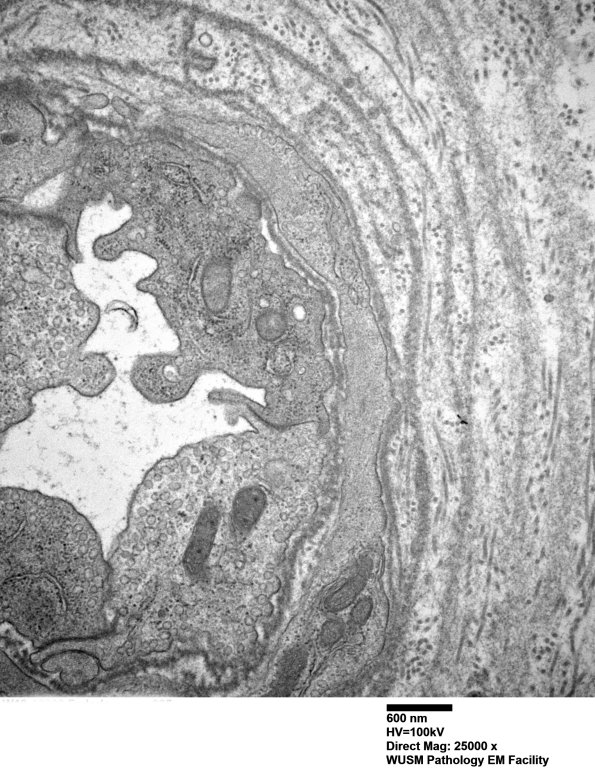

The endoneurial vessels show thickening by concentric proliferation of basal lamina. (electron micrographs)